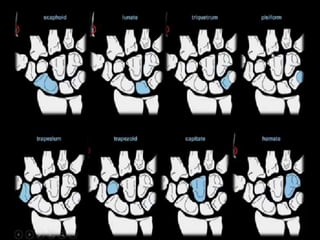

A simple approach is to consider the lunate

which is usually the easiest carpal bone to

visualize on a lateral wrist image. If the

lunate is abnormally tilted in a dorsal

direction on a standard lateral wrist image,

a DISI should be considered. If the lunate is

abnormally tilted in a volar direction a VISI

should be considered. DISI is due to

disruption of the scapho-lunate articulation.

VISI is secondary to disruption of the luno-

triquetral articulation.